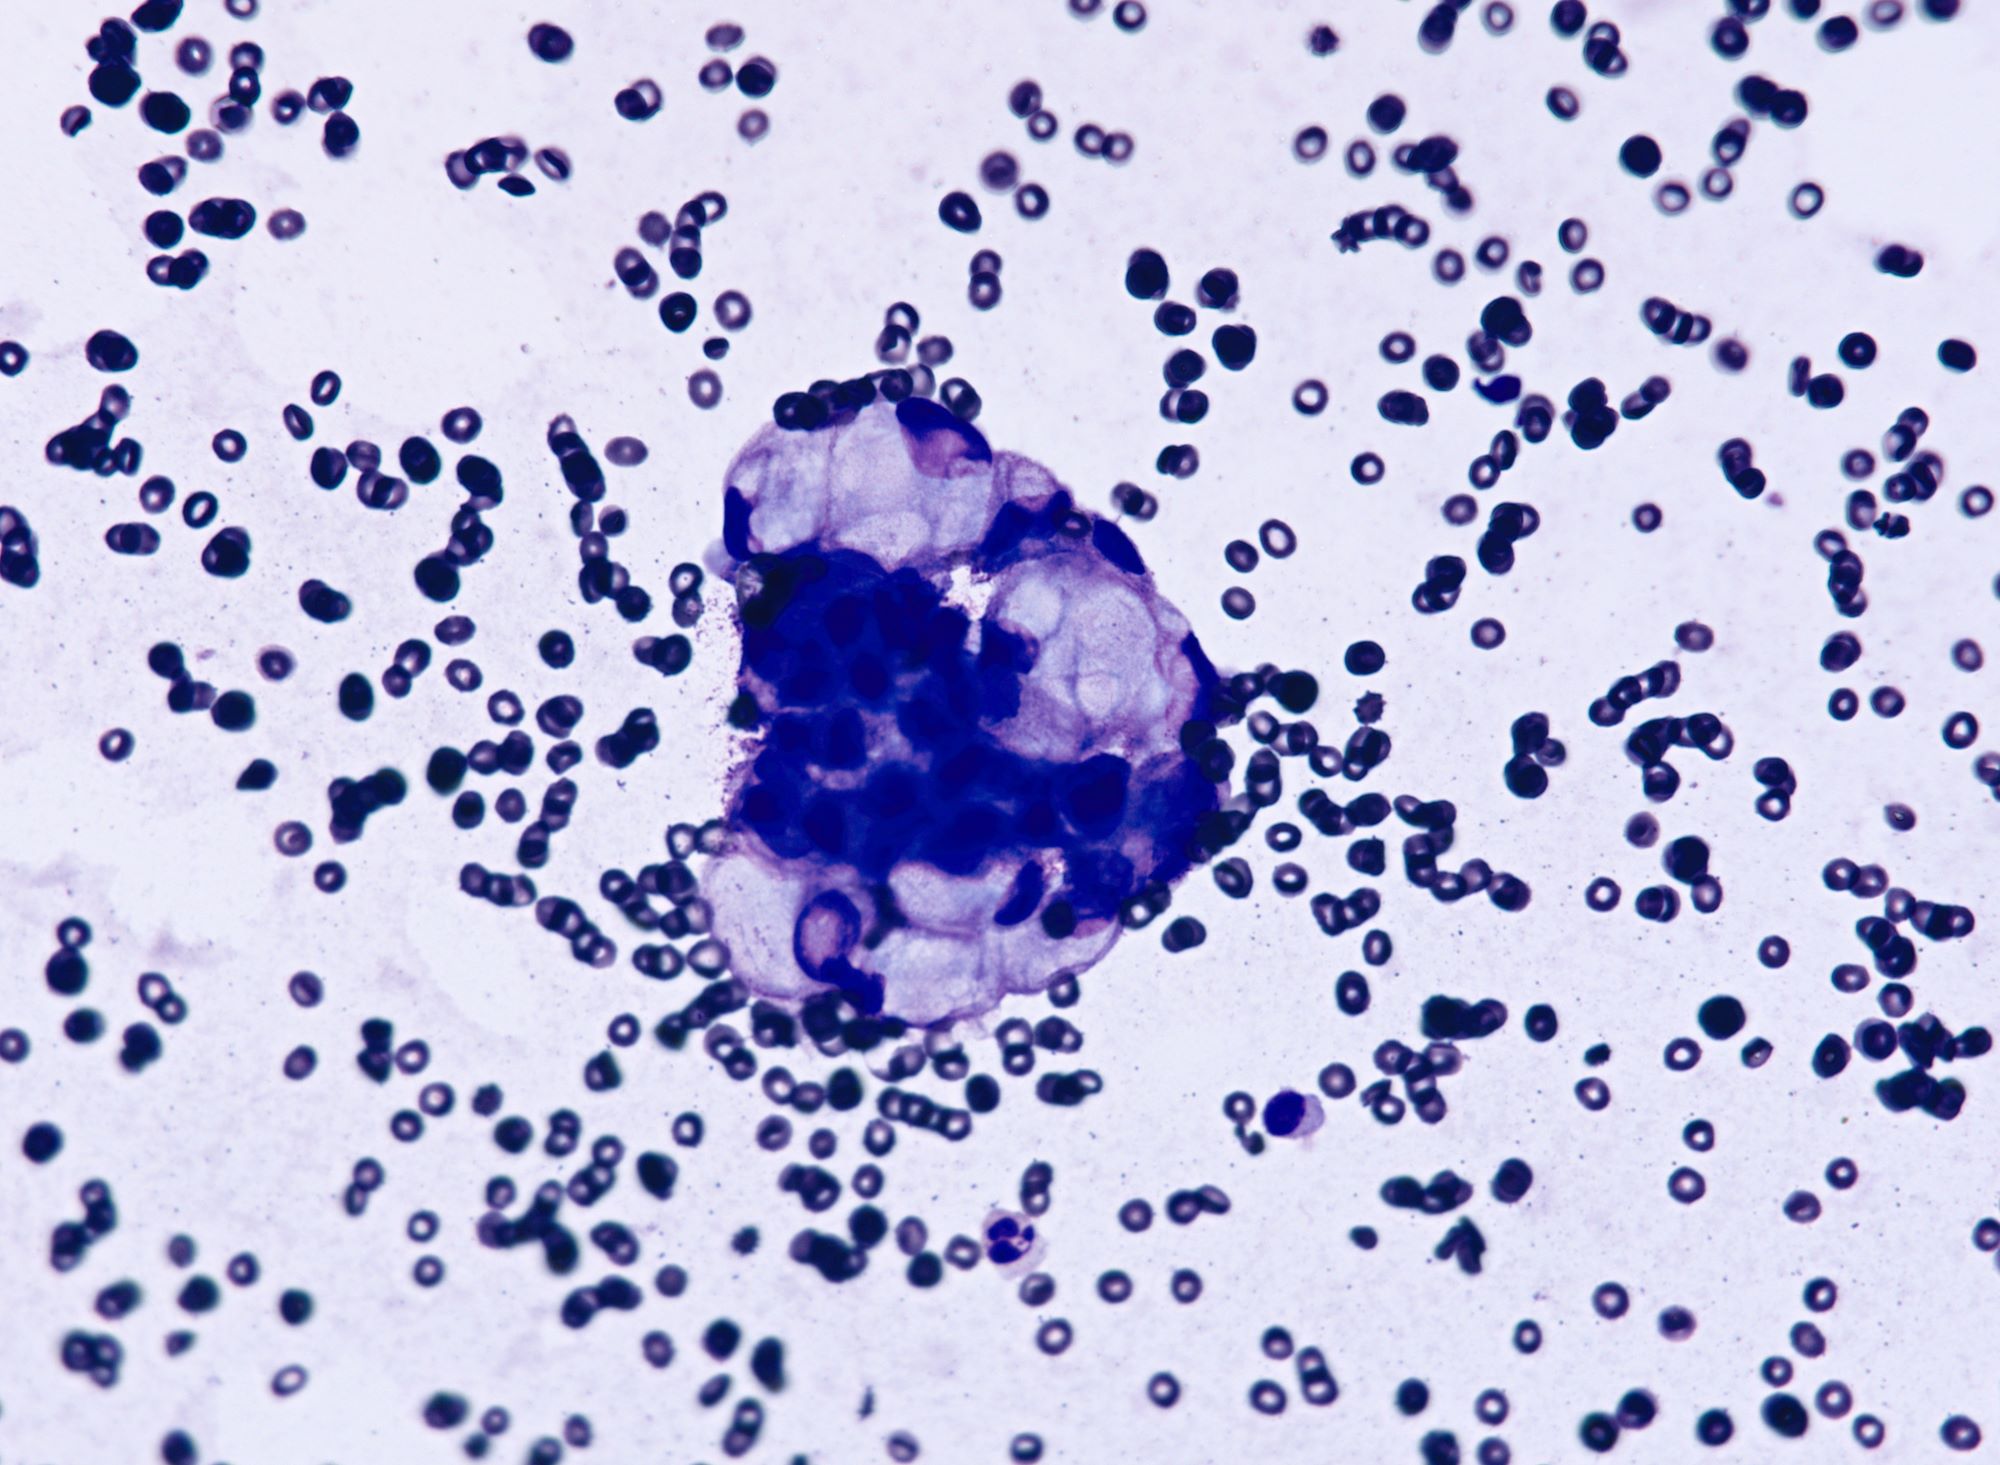

Cytology description

- Malignant glandular cells in clusters and singly

- Moderate amounts of finely vacuolated cytoplasm

- Enlarged hyperchromatic nuclei

- No significant nuclear pleomorphism (< 3x variation in size)

- Prominent nucleoli

Cytology images